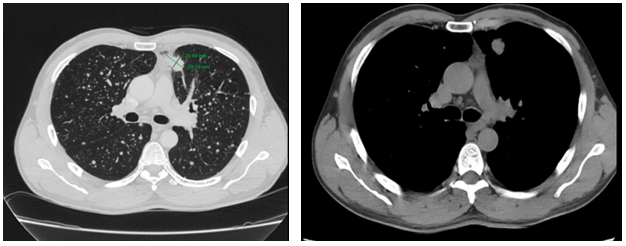

-         MRI sọ não:

Hình 4. Trên phim chụp MRI sọ não: Rải rác trong nhu mô trên và dưới lều có các nốt ngấm thuốc, lớn nhất vị trí cạnh não thất bên bên phải đường kính ~11mm – Theo dõi tổn thương thứ phát

Cộng hưởng từ sọ não:

Sau 6 tháng điều trị: Nhu mô não vùng trên và dưới lều tiểu não: hình dạng và cấu trúc bình thường, tín hiệu đồng nhất, ranh giới chất trắng và chất xám rõ. Không thấy tổn thương khu trú hoặc lan tỏa.